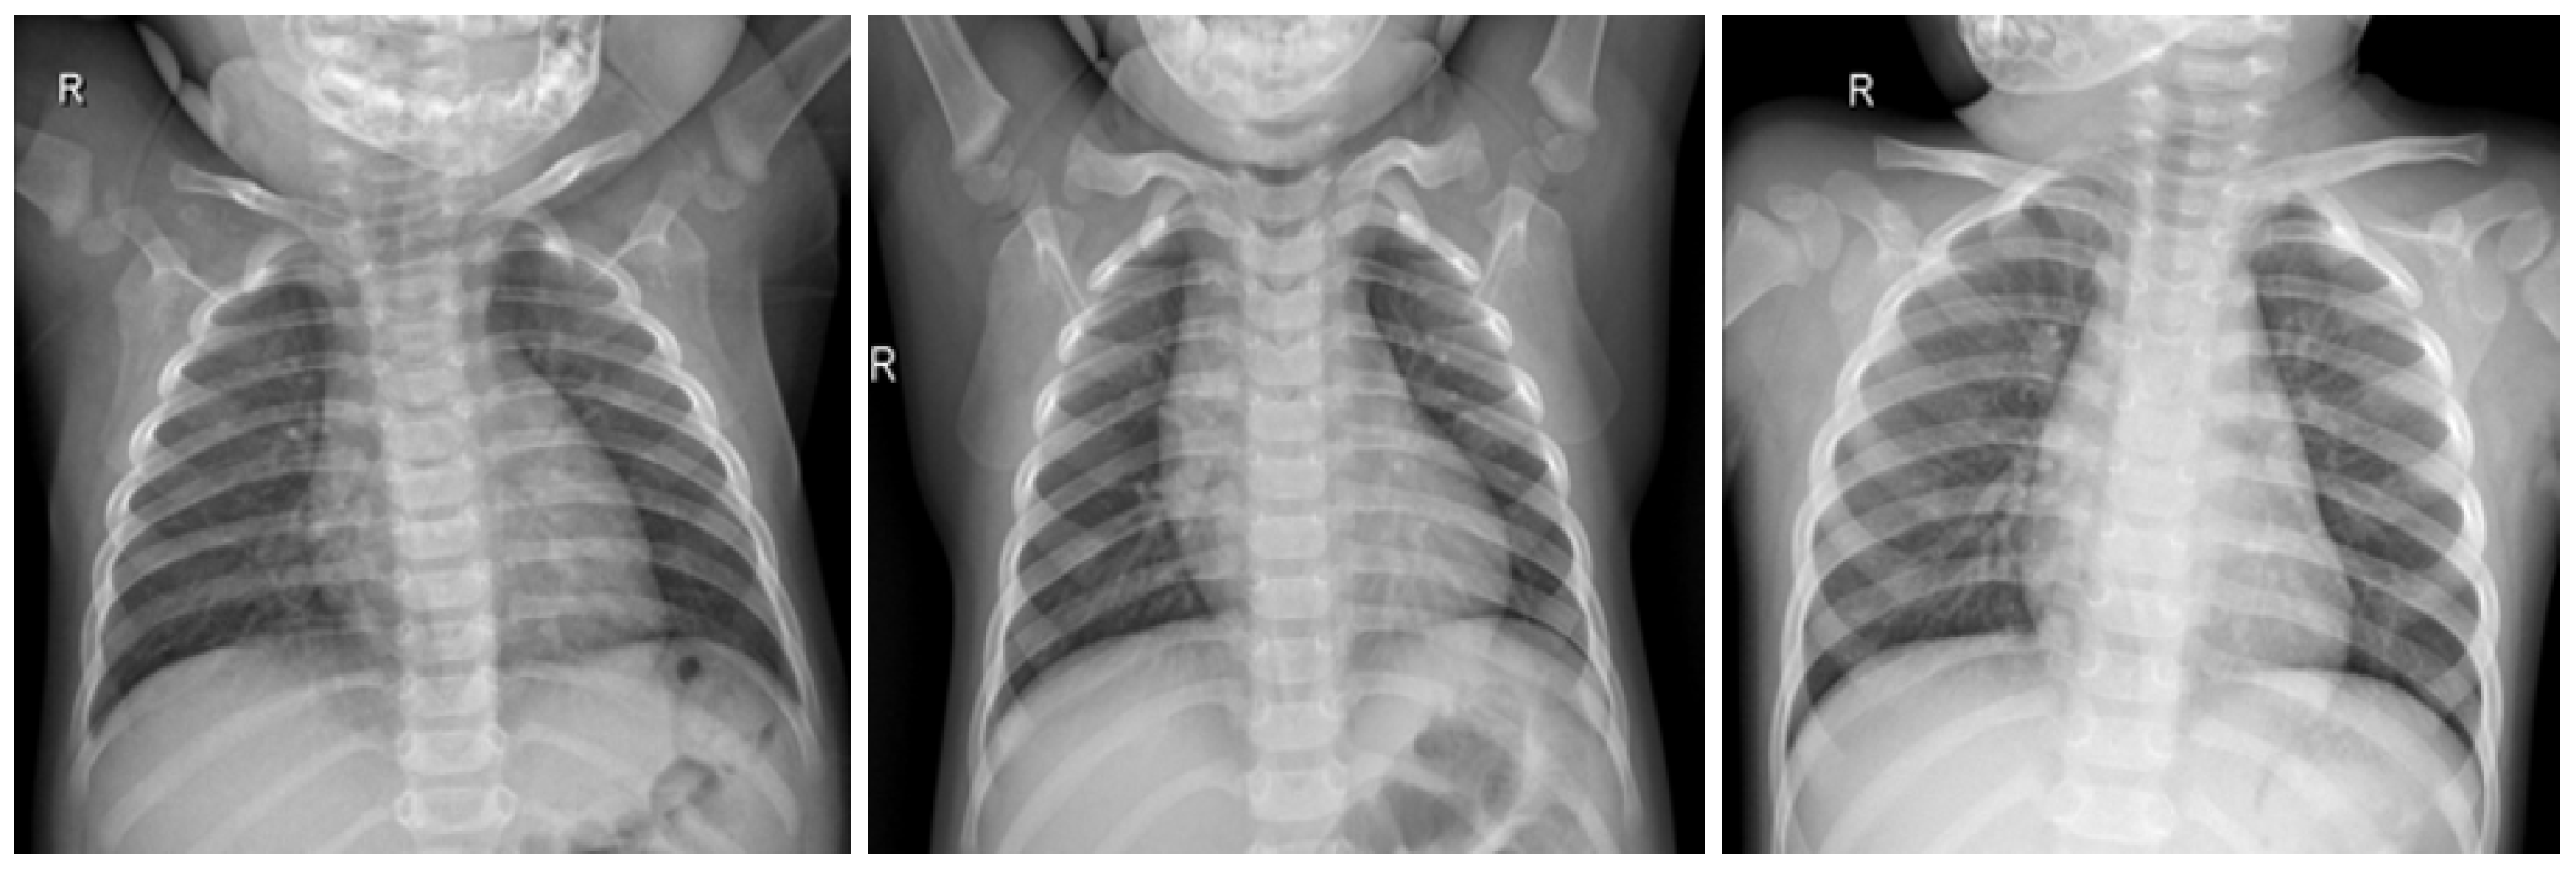

In this work, a COVID-19 radiography dataset collected in previous works related to a COVID-19 detection model [24,25] was used. The dataset contains X-ray lung images with four different classifications, which are COVID, Lung_OPACITY, Normal, and Viral Pneumonia. In this work, we utilized two classifications, which are COVID and Normal, focusing only on the COVID-19 detection machine learning process.

Figure 3.

COVID-19 positive X-ray image dataset samples.